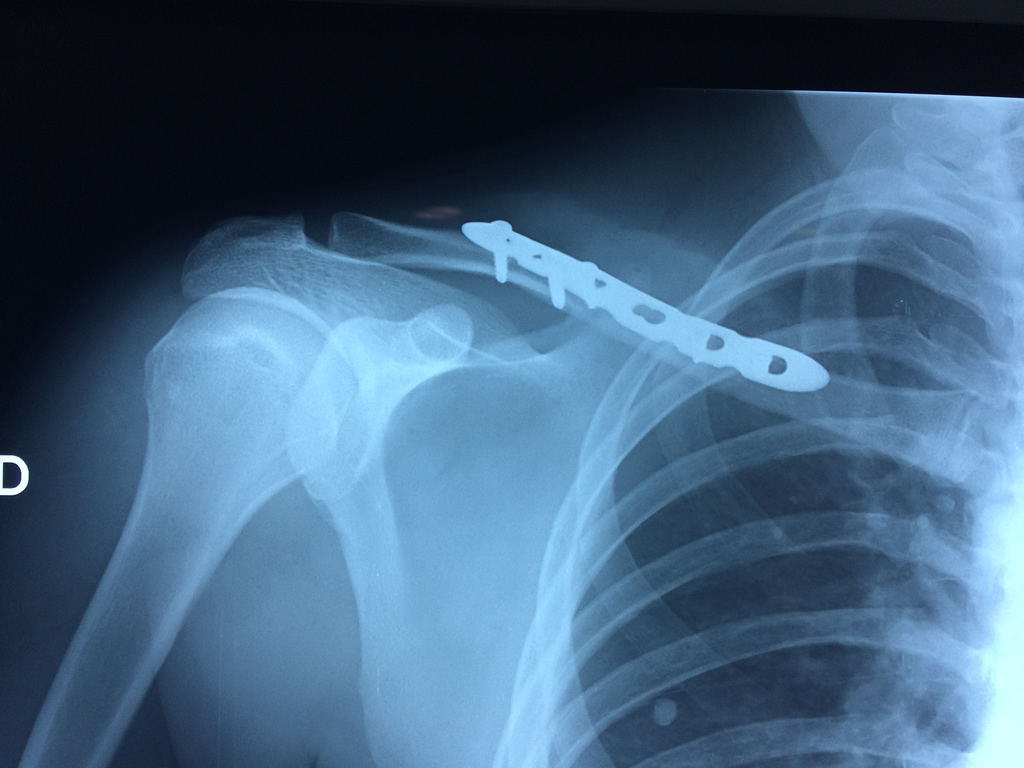

Cirugias en El Salvador - Clavícula